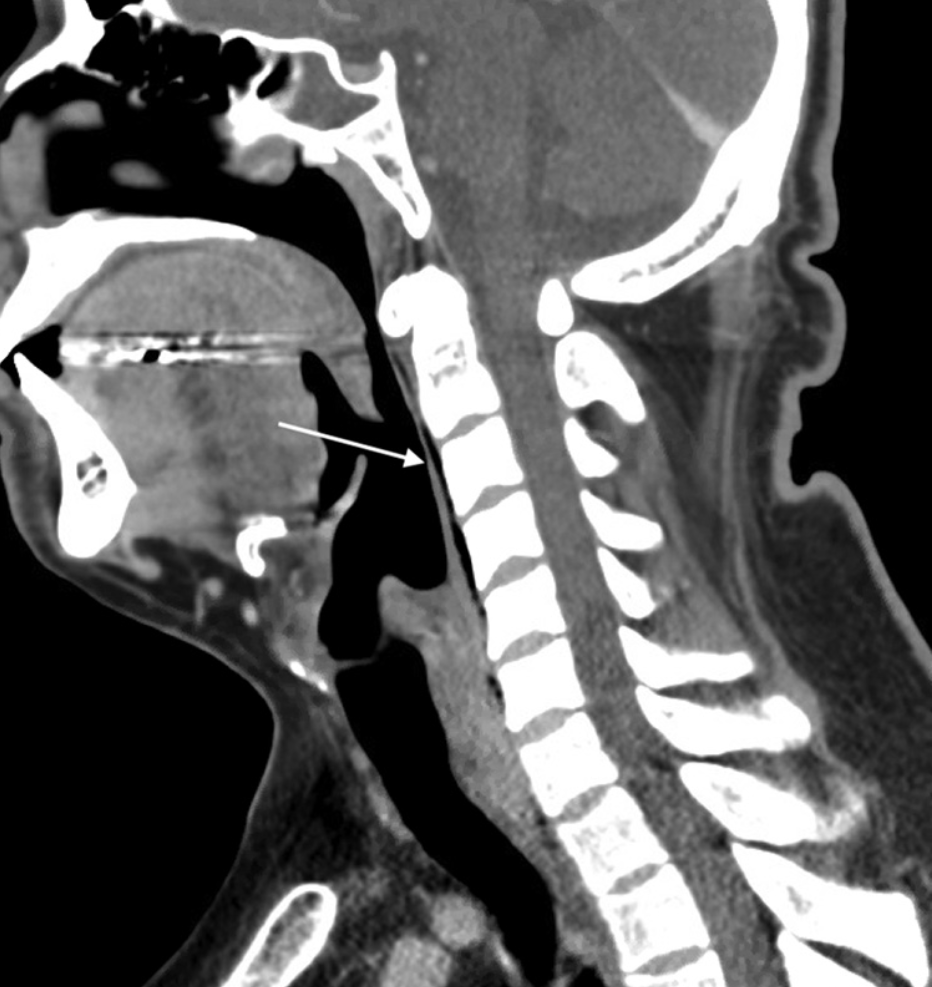

- A 30-year-old man presented to the emergency department with throat pain and oral intolerance of fluids for several hours. Earlier that day, an outpatient operation was aborted after multiple unsuccessful intubation attempts in the operating room. The patient had unremarkable vital signs, noting only odynophagia. Computed tomography (CT) of the neck and an esophagram with water-soluble contrast were acquired.